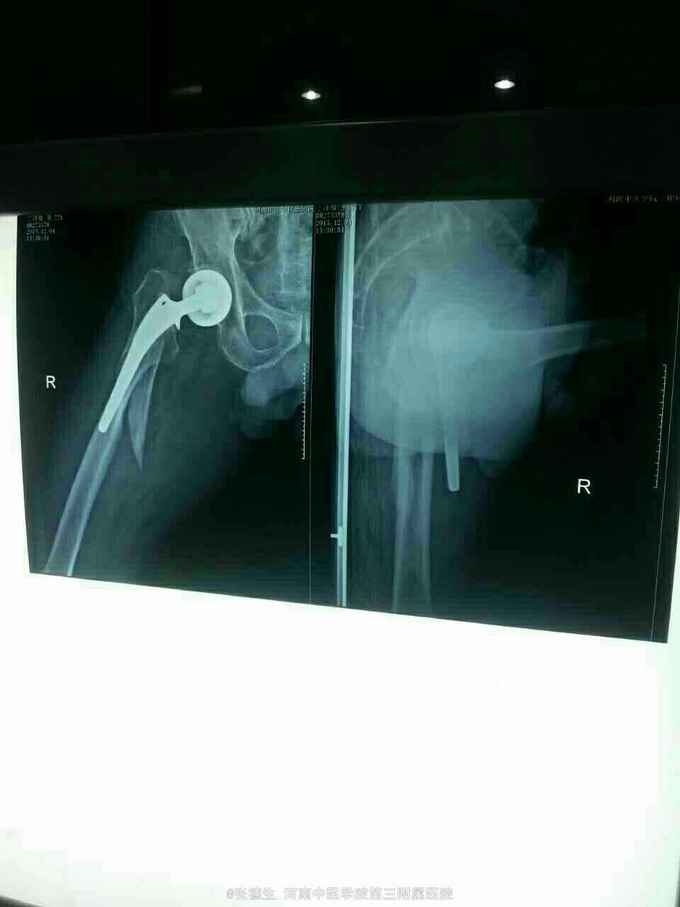

外伤后右髋部疼痛1天 患者男,77岁,五年前曾因股骨颈骨折行右股骨头置换术,1天前不慎摔倒,致右髋部疼痛,急来院,门诊拍片示右股骨假体周围骨折。

右股骨假体周围骨折 切开复位锁定板加扎带内固定术